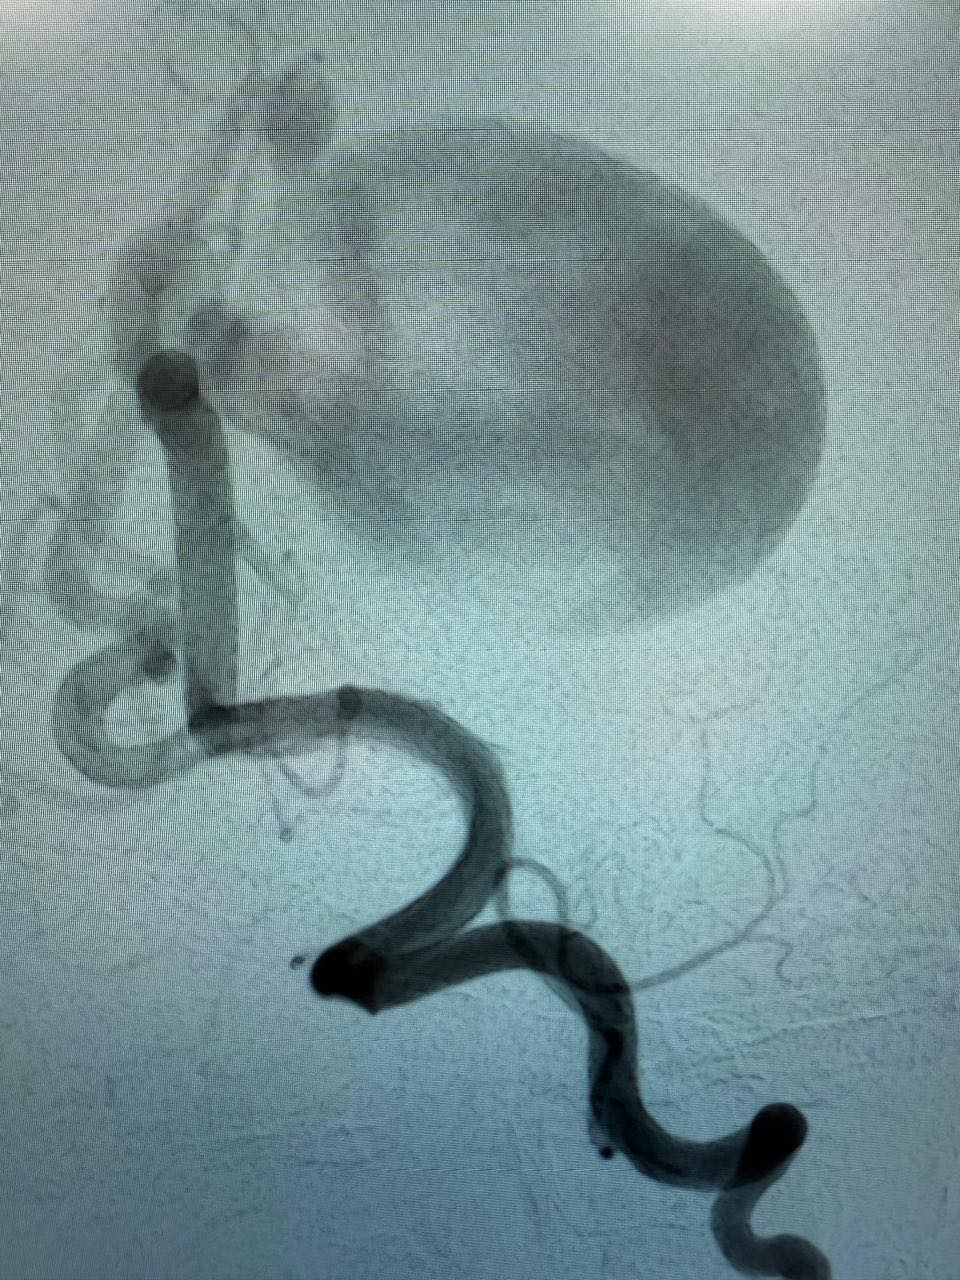

أعلنت وزارة الصحة والسكان عن نجاح فريق طبي بمستشفى العاصمة الإدارية، التابع للهيئة العامة للتأمين الصحي، في إجراء قسطرة مخية علاجية لطفلة تبلغ من العمر 6 أشهر تعاني من حالة نادرة وخطيرة من التشوه الوريدي بالمخ، وهي حالة تهدد النمو الذهني والحركي للأطفال.

وقال الدكتور حسام عبدالغفار، المتحدث الرسمي لوزارة الصحة والسكان، إن الفريق الطبي نجح أيضًا في إجراء قسطرة مخية لطفل آخر يبلغ من العمر 12 عامًا يعاني من تشوه شرياني وريدي، بالإضافة إلى علاج مريض يبلغ من العمر 51 عامًا كان يعاني من تمدد شرياني بالمخ،حيث تم تركيب دعامة لتحويل المسار الدموي، في إجراء يُعتبر من التقنيات الحديثة في مجال القسطرة المخية لعلاج تمدد الشرايين.

وفي السياق ذاته، أشار الدكتور رمزي منير، مدير مستشفى العاصمة الإدارية، إلى أن قسم الأمراض العصبية بالمستشفى يضم وحدة متكاملة لعلاج السكتة الدماغية تقدم خدمات شاملة، من بينها حقن العقاقير المذيبة للجلطات، والقسطرة المخية لسحب الجلطات الحادة، بالإضافة إلى علاج تمدد الشرايين والوحمات الدموية والناسور الشرياني الوريدي، كما يضم القسم وحدة أبحاث متخصصة في فسيولوجيا الأعصاب، تشمل اختبارات مثل رسم المخ الروتيني والمطول ورسم الأعصاب والعضلات.